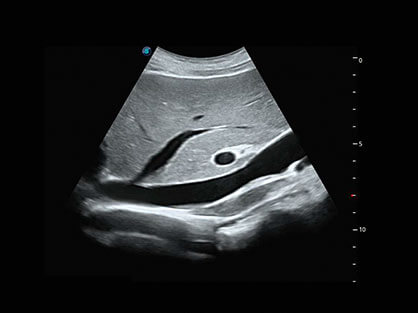

宽频带腹部凸阵探头和腹部容积探头、大角度腔内探头和腔内容积探头、独特的生殖专用曲柄探头,为妇产应用提供全面诊疗方案。

卵泡结构的自动识别和测量,可显示多组测量数据。